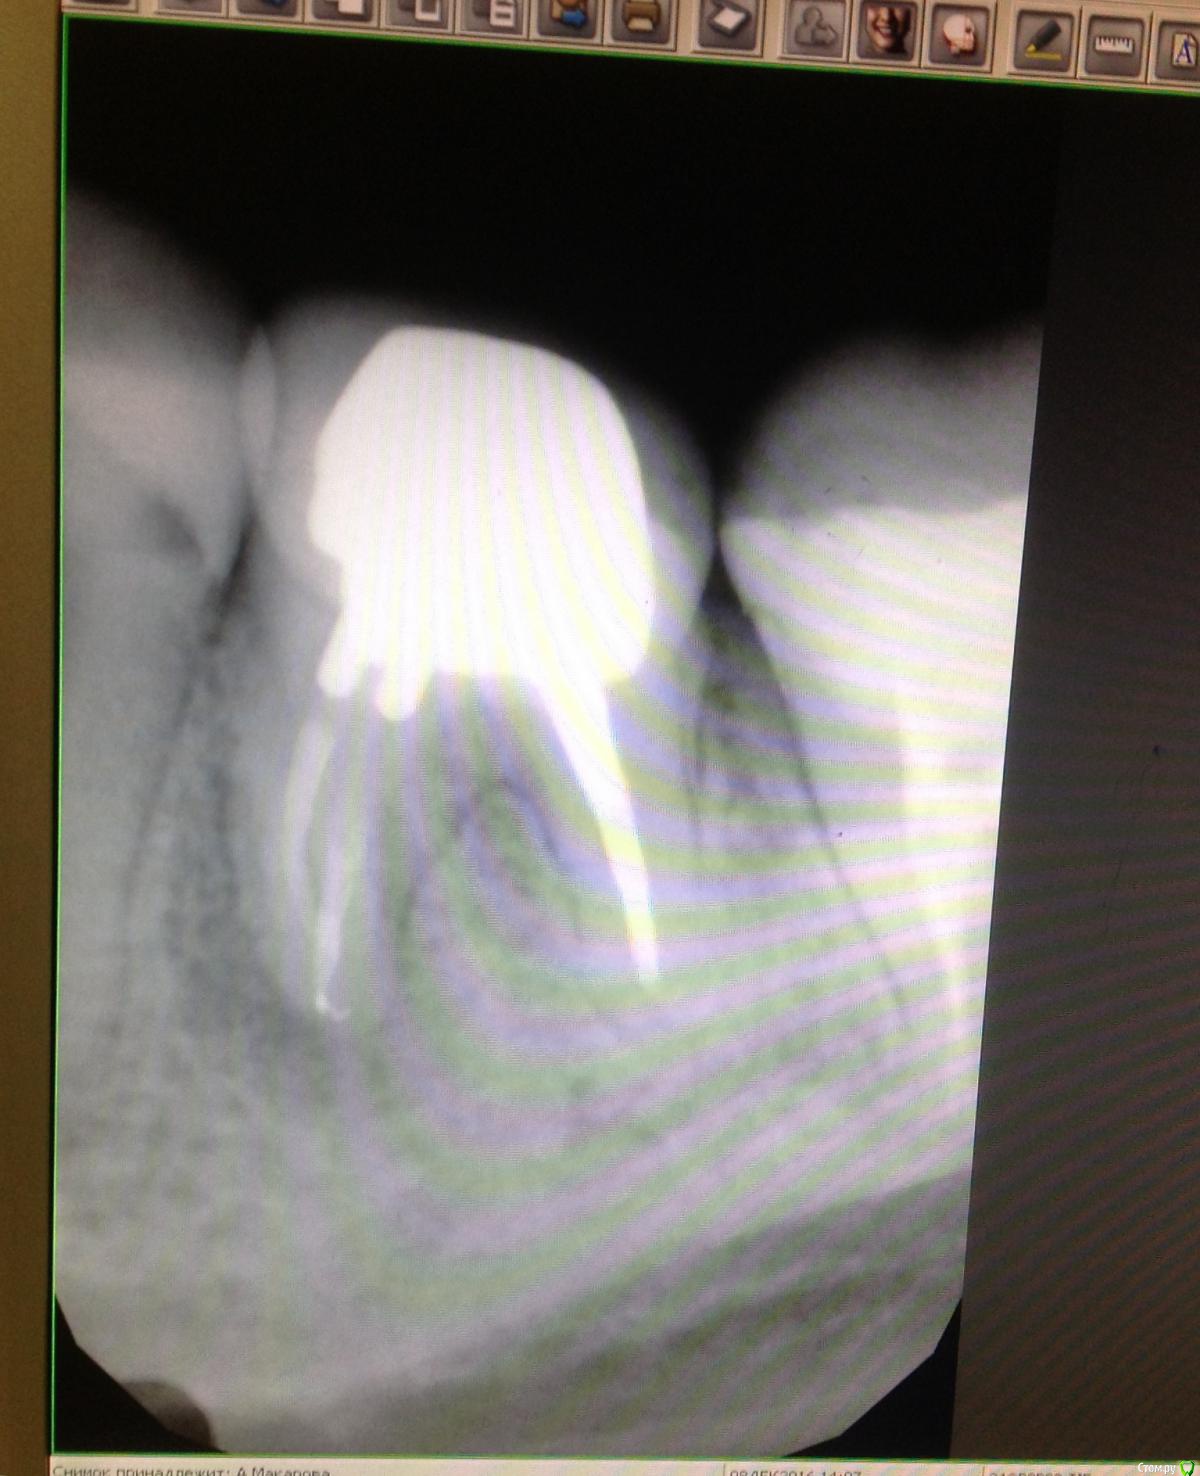

Сашуля Опубликовано 8 декабря, 2016 Поделиться Опубликовано 8 декабря, 2016 (изменено) Здравствуйте уважаемые стоматологи.Очень хочется получить совет.Имею хронический периодонтит. Температура 37,3 постоянно, впрочем, это мне не мешает.Первое фото. Когда обнаружили периодонтит. 2013 год.Второе фото-в процессе лечения.Мне запломбировали каналы, постави вкладку, налили пластиковую временную коронку и отправили в свободное плавание. Зуб никак не беспокоил.Наблюдалась, делала снимки с определённой периодичностью. Зуб не беспокоил.Сейчас настал решающий момент. Последние два снимка были сделаны сегодня. Сторона с проблемным зубом ноет, непонятно, что это болит, толи соседние зубы, толи периодонтит беспокоит. Боль усиливается к вечеру. При надавливании на проблемный зуб острая боль. При внешнем осмотре всё в норме.Вообще грозятся удалять или сделать Гемисекцию. Чего мне ожидать, может быть можно по данным снимкам чтото выяснить.Спасибо. Изменено 8 декабря, 2016 пользователем Сашуля Ссылка на комментарий

DmitrySH Опубликовано 8 декабря, 2016 Поделиться Опубликовано 8 декабря, 2016 Последний снимок не четкий. Видимо нужна ревизия каналов. Еще 5тый зуб, кариес под пломбой 1 Ссылка на комментарий

IvanK Опубликовано 8 декабря, 2016 Поделиться Опубликовано 8 декабря, 2016 Последний снимок выглядит не плохо, я бы сделал кт скорее всего у Вас пульпит 5го Боль усиливается к вечеру. 1 Ссылка на комментарий